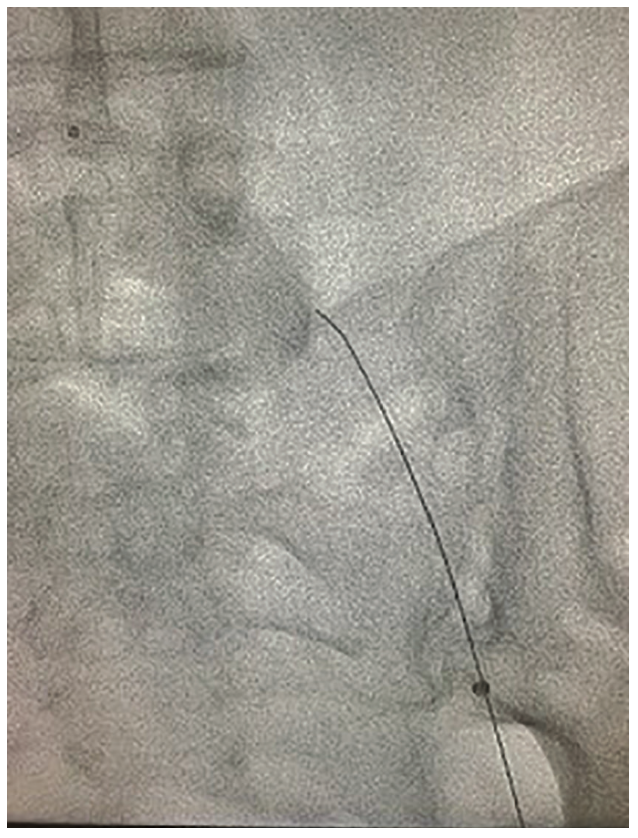

The .035-inch microcatheter was advanced from the contralateral sheath to the bifurcation and the retrograde wire was advanced into the microcatheter. The .035-inch catheter was then advanced over the retrograde wire beyond the distal cap. The retrograde wire was removed, and an antegrade .014-inch ViperWire (CSI) was advanced and externalized. The Touhy Borst adaptor was placed on the externalized wire to prevent withdrawal and allowed work to be performed over the wire in a typical antegrade fashion. A 1.5 Auryon laser (AngioDynamics) (Figures 3-4) was used to perform atherectomy for a total time of approximately 3 minutes. Following atherectomy, a 6.0 mm x 240 mm noncompliant balloon was utilized to dilate the vessel. Inflation at 4 atmospheres resulted in patient pain, but a slightly higher pressure was done at the stent overlap. Angiography revealed brisk flow through the vessel, but there was clearly dissection proximal to the previous stents. Two prolonged inflations of 5 minutes were performed without significant improvement in the dissection. A stent was subsequently placed to address the dissection, followed by postdilation with the balloon at higher pressure, which resulted in good flow through the vessel without any residual angiographic dissection (Figure 3).